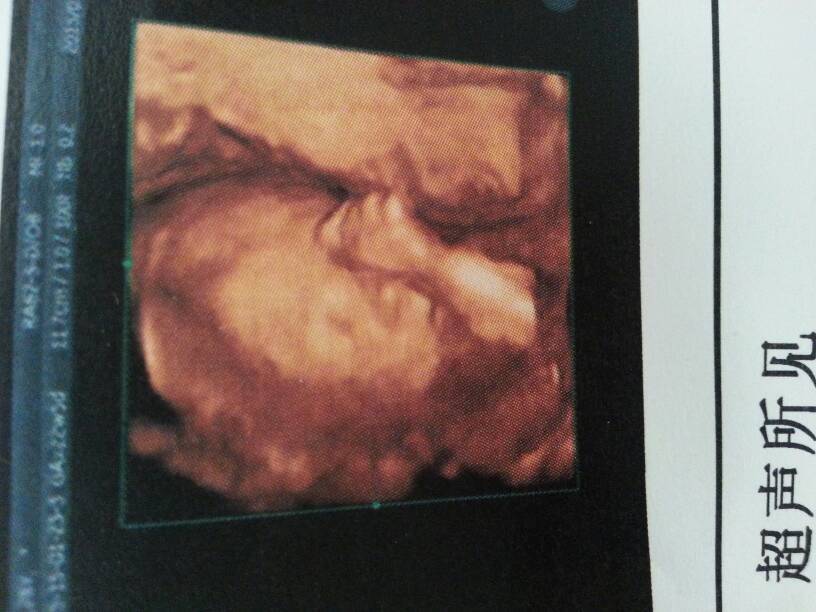

周五去医院做四维,医生说是儿子…来给大家晒晒儿子的照片 周五去医院做四维,医生说是儿子……来给大家晒晒儿子的照片 点击展开 这小女子贼可爱 2015-01-25 18:58 为您推荐: 其他回答 几个月了宝妈? 只爱老公一个 2015-01-25 22:19 祝宝妈好运哦 阿梦梦 2015-01-25 20:52 祝贺你。。。 151*****830_x1fy 2015-01-25 20:03 恭喜,宝妈!!! 妞妞爱妈妈 2015-01-25 20:01 你们医生还告诉这个? 小可人@.@ 2015-01-25 19:34 加载更多 相关问题 昨天做四维彩超说胎儿心脏可能有问题,因为宝宝当然是趴着的,医生说看不清,叫我周五的时候再去做一次确 今天去医院看看做四维结果医生说做不了了说已经过了做四维的时候了,还叫我去别的医院看看 这个四 今天做了四维彩超,但是医生说还让做心脏彩超 有必要吗?想问下大夫 照片上什么都正常,不做可以吗?